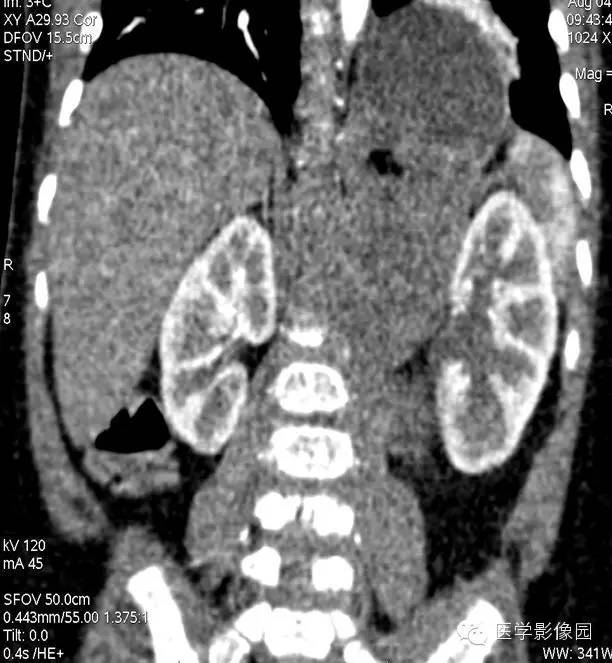

7——增强冠状位重建

小儿畸胎瘤好发于身体中线及两旁,多发生在骶尾部、腹膜后、纵隔、卵巢等部位,是腹膜后常见的实体瘤之一,发病率仅次于肾母细胞瘤和神经母细胞瘤。

畸胎瘤是由两个或三个原始胚层组织演化而来的胚胎性肿瘤,大体上囊性、实性或囊实性兼有。囊性畸胎瘤又称皮样囊肿,仅含表皮及其附属成分,基本上均为良性。实性畸胎瘤含有三个胚层成分。按组织学分类可分为良性畸胎瘤和恶性畸胎瘤。良性畸胎瘤由分化良好的成熟组织构成,故又称为成熟畸胎瘤,瘤体囊性部分多于实质部分,小儿中绝大部分均为良性畸胎瘤。恶性畸胎瘤由胚胎发生时期的未成熟组织构成,实质部分常多于囊性部分,恶性畸胎瘤在小儿中十分少见。小儿畸胎瘤以女性多见,男女之比约为1:3-4,腹部包块和腹胀为腹膜后畸胎瘤主要的临床表现,患儿一般状况良好。